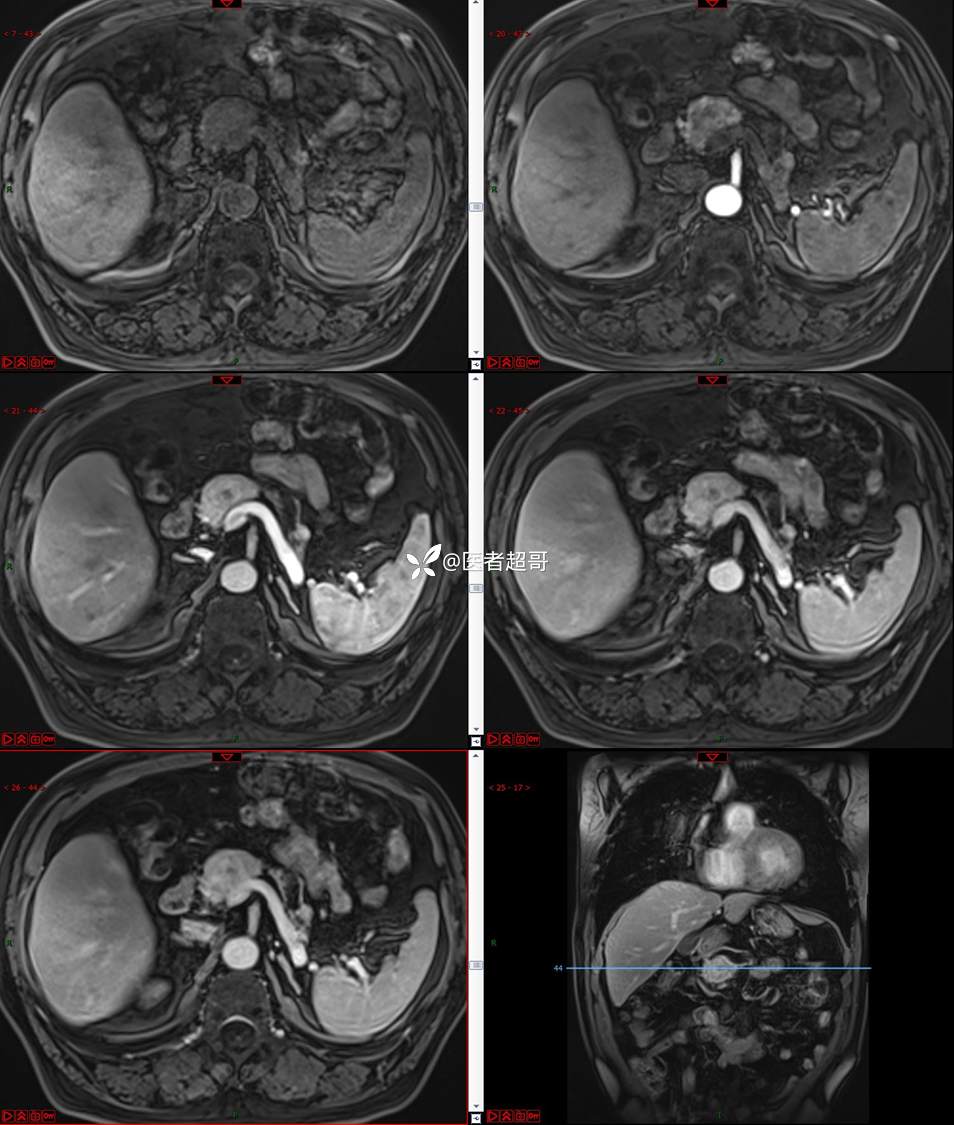

【影诊笔记677】查体发现胰腺占位性病变1周,细节决定成败,请诊断分析!

主 诉:查体发现胰腺占位性病变1周。

现病史:患者1周前在当地查体时发现胰腺占位性病变,无恶心、呕吐,无腹痛,无寒战、高热,无咳嗽、咳痰等异常不适,来我院门诊查上腹部CT平扫+强化:胰腺尾部异常密度灶。今为求进一步治疗,门诊以“胰腺占位性病变”收入院。患者自发病以来,一般情况可,神志清,精神可,普通饮食,二便正常,体重及体力无明显改变。

既往史:既往糖尿病病史2年,口服二甲双胍早晚各一片和格列吡嗪早晚各一片,否认高血压、心脑血管病等疾病史,否认肝炎、结核或其他传染病史及密切接触史,预防接种史不详,否认药物及食物过敏史,否认外伤史,12年前肾癌切除术手术史,否认输血史,其它无特殊。